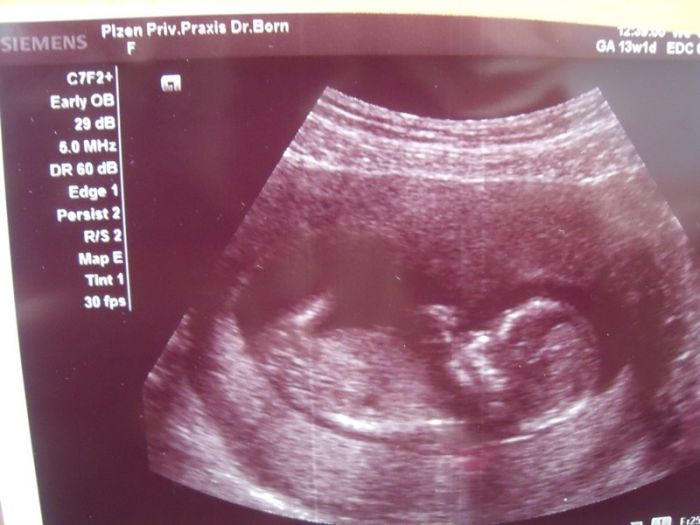

a bohužel pro častý krvácení a bolest v podbíšku jsem už měsíc doma, nic moc, ale prcek je v pořádku .. termín porodu mi vychází na 6.5... před dvěma týdny jsem byla na screeningu a už mi na 99% ukázala, že to bude kluk :))) přidávám fotku z posledního utz z 30.10.